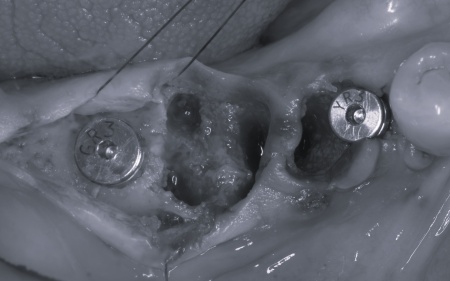

①入れ歯 ②インプラント それぞれのメリットとデメリットをお伝えしたところ、患者様は「できるだけ違和感がなく噛めるようになりたい。またなるべく短期間で治療を終えたい」と希望されたため、抜歯と同時にインプラントを埋め込む抜歯即時埋入法を提案し、同意いただきました。 まず、右下奥歯(第2小臼歯、第1大臼歯)を抜きます。 抜歯後にできた穴とインプラントの間には隙間が生じるため、骨の再生を助ける目的で骨補填材を使用しながら、丁寧に縫合しました。 3ヶ月後、インプラントと骨がしっかりと結合したことが確認できたため、被せ物を作製するための型取りを行います。 後日、完成した被せ物を装着し、見た目や噛み合わせに問題がないことを確認して、治療を終了しています。 |